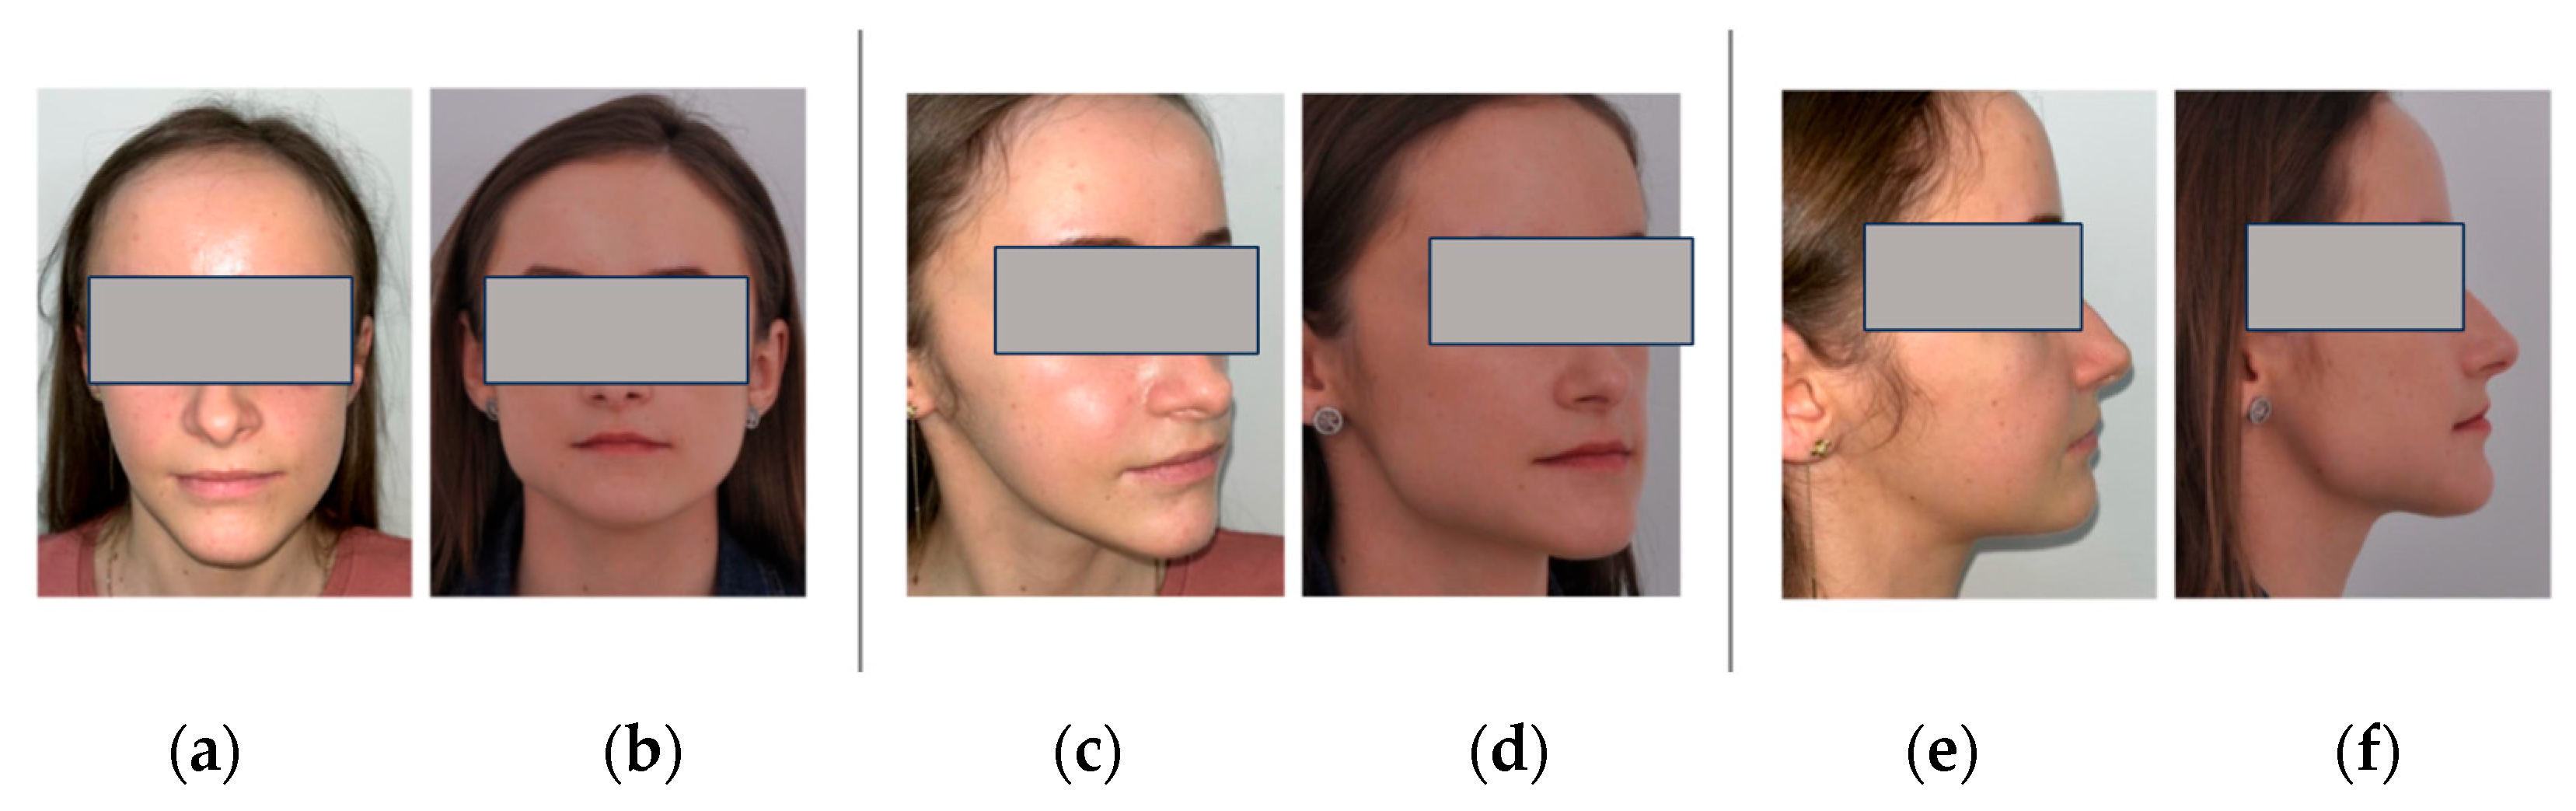

2. Case Report